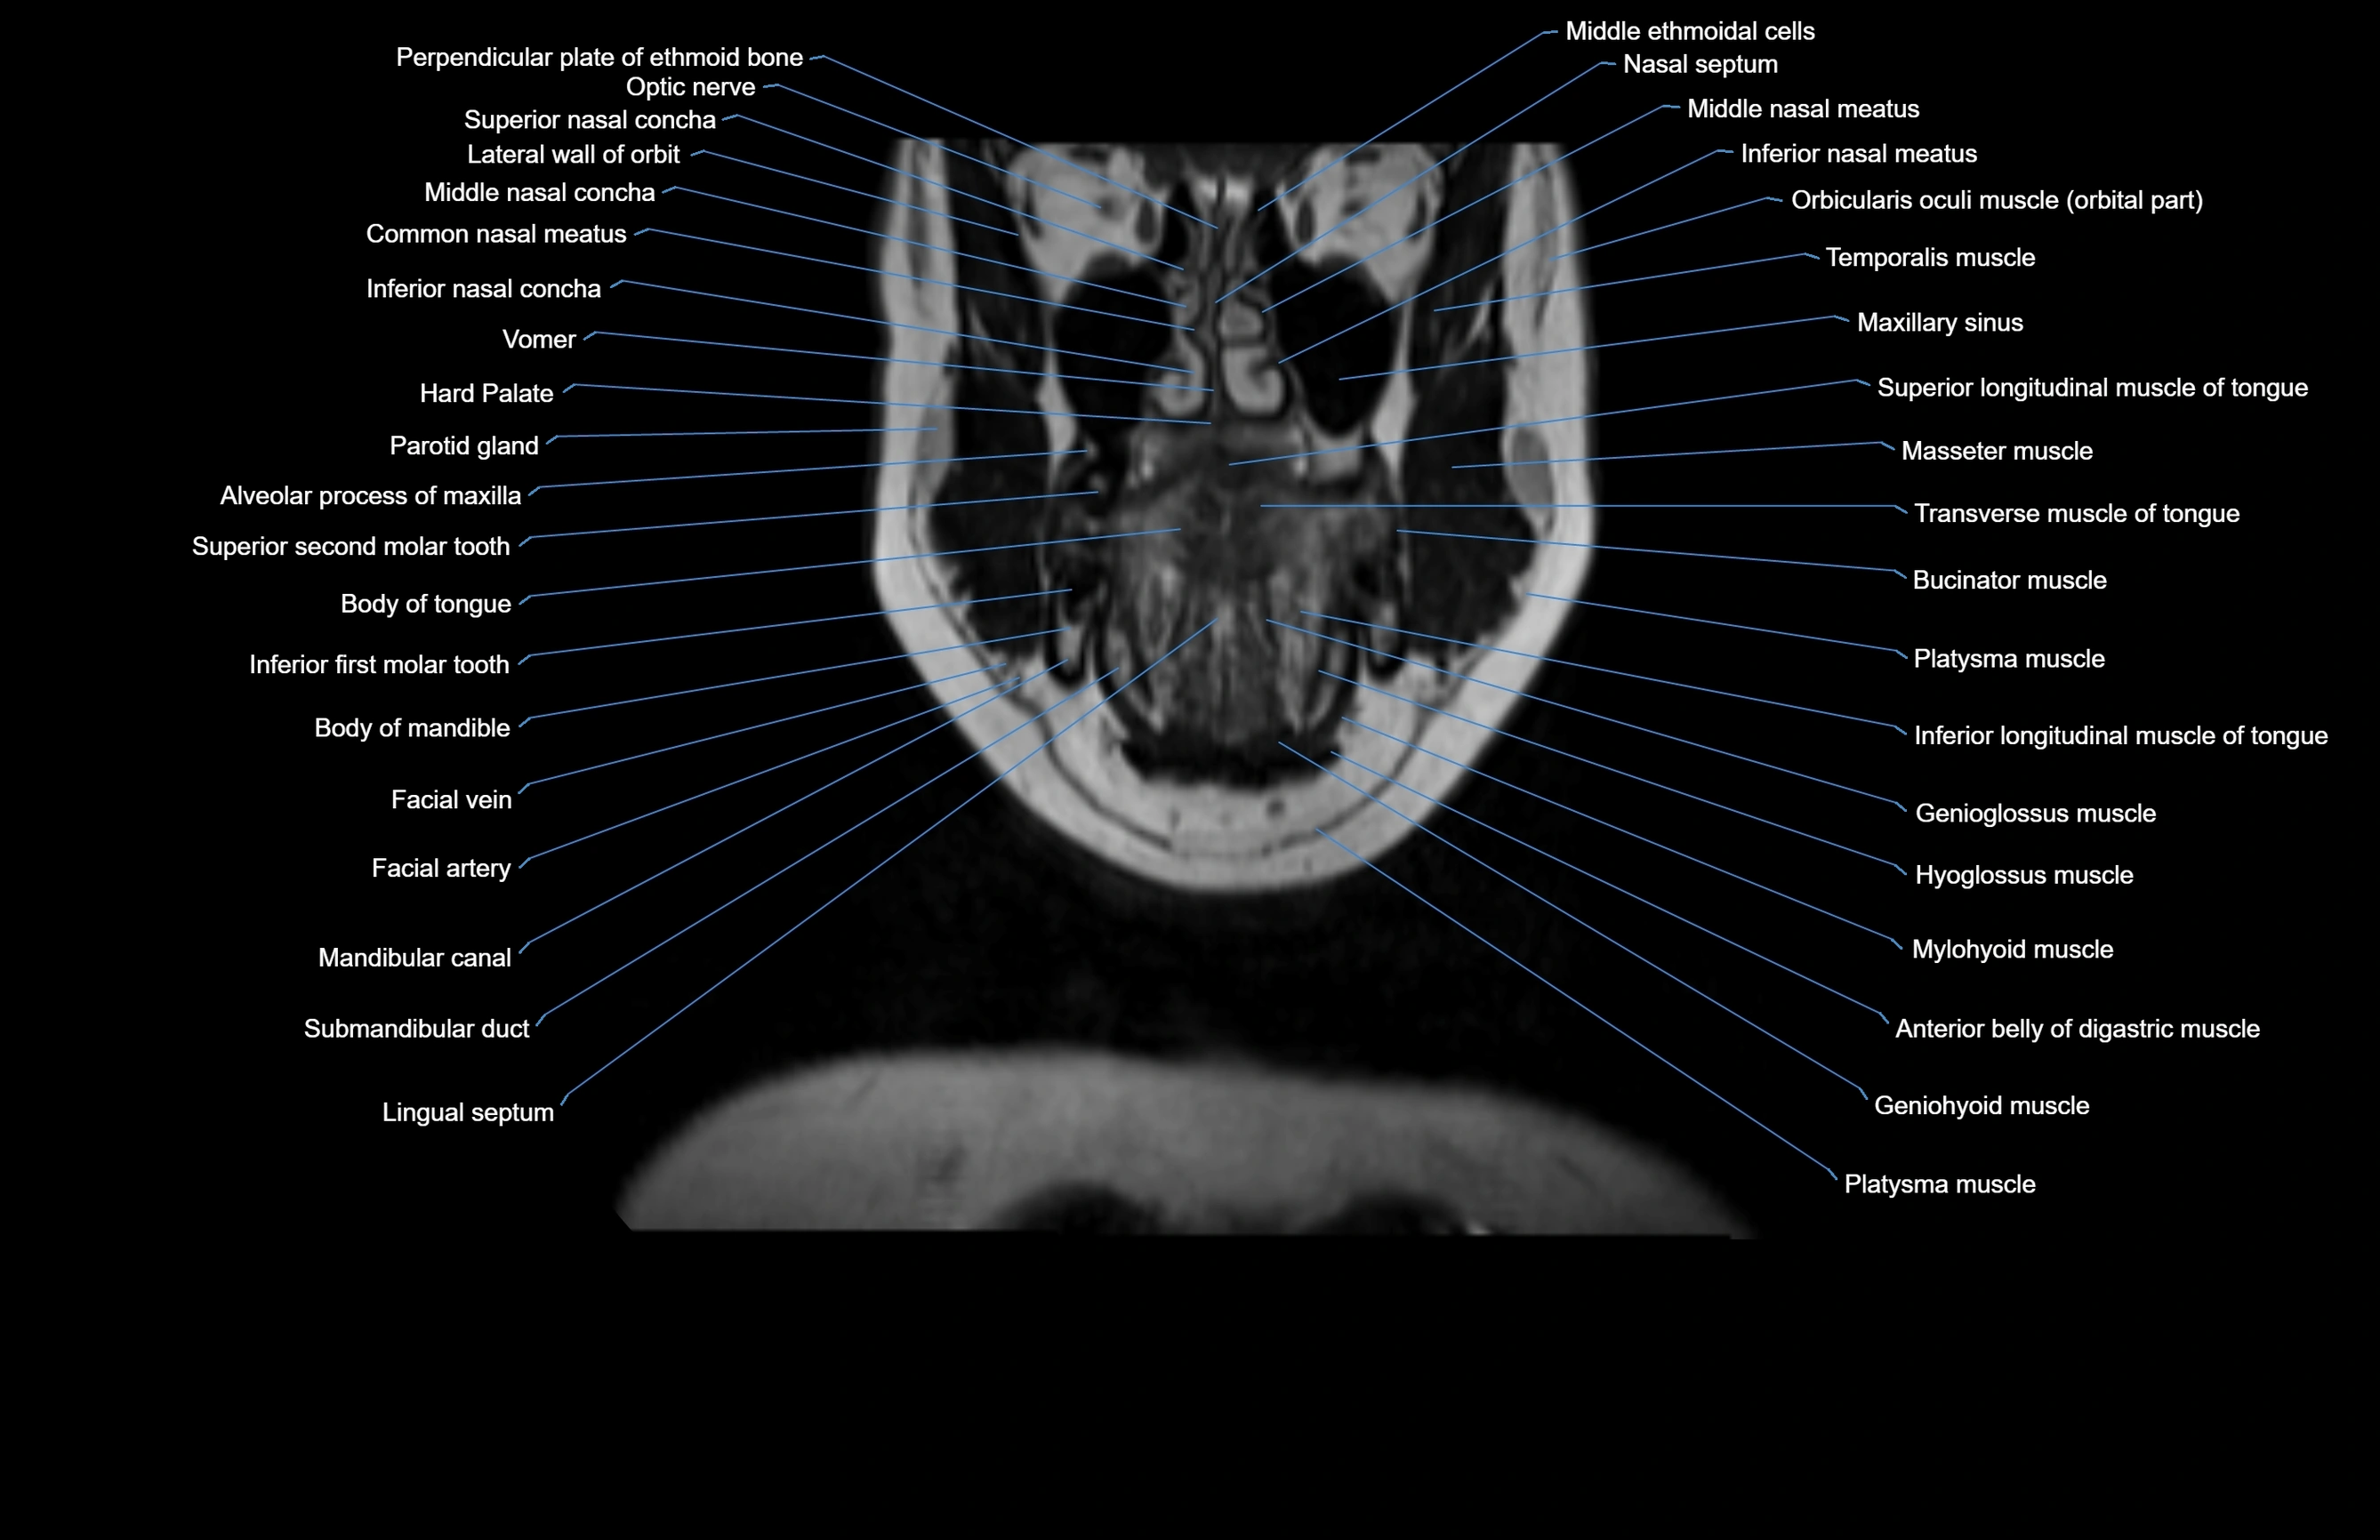

- Alveolar process of maxilla

- Body of mandible

- Body of tongue

- Buccinator muscle

- Common nasal meatus

- Facial vein

- Genioglossus muscle

- Hyoglossus muscle

- Inferior longitudinal muscle of tongue

- Inferior nasal concha

- Inferior nasal meatus

- Mandibular canal

- Maxillary sinus

- Middle nasal concha

- Mylohyoid muscle

- Nasal septum